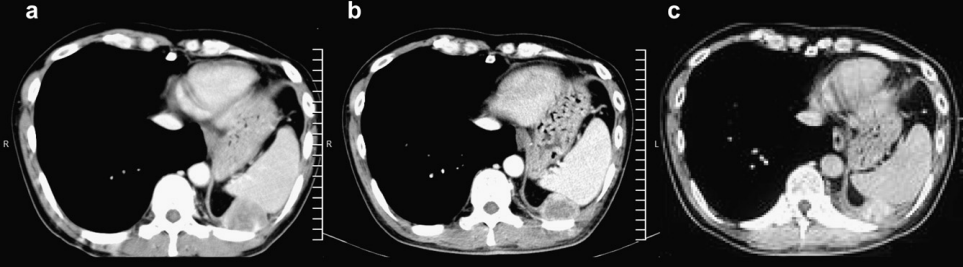

一位78岁女性上唇肿块形成3个月,经过检查发现,在左上中切牙至尖牙区域的唇颊沟处有一形态不规则的肿瘤样肿物。活检后,诊断为乳头状囊腺癌。患者拒绝接受手术治疗、化疗及放疗。之后肿瘤在三年半的时间里逐渐增大,在拒绝接受手术的情况下,患者最终同意接受硼中子俘获疗法(BNCT)。